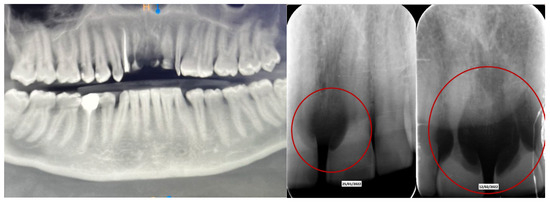

60 days after the extraction of the upper front teeth, it was discovered that the upper right premolars were also affected by significant root resorption, as well as 46 and 47 (Figure 6).

Based on previous experience and the speed of their development, in January 2023, it was decided to extract teeth 14 and 15, 46 and 47, decontaminating the alveoli, regenerating with PRF (in order to promote healing of the defect) and heterologous bone. So, the site was treated with a mix of Bio-Oss granules 25 (Geistilich Bio-Oss-Geistlich Pharma AG, Wolhusen, Switzerland), autologous bone chips, platelet-rich fibrin (PRF), and collagen membranes (45% Bio-Oss 25, 45% PRF, 10% autologous bone chips). Simultaneously, four implants (3.6 × 10 mm, Biotech Dental, Allée de Craponne, Salon de Provence, France) were inserted in the upper edentulous area, completely submerging them. However, an initial rejection of three of the four implants was observed (about 20 days after insertion), which made it necessary to remove them, decontaminate them with dye-free photodynamic therapy, and reinsert them 120 days later, when the implants were also inserted in areas 46-47 (3.6 × 10 mm and 4.2 × 10 mm, Biotech Dental, Allée de Craponne, Salon de Provence, France) in June 2023 (Figure 7).

Figure 6. Evolution of the external resorptions in 46-47.

The case has now been finalized, and the radiographic follow-up shows a stability of the bone regenerations obtained (Figure 11), with no new external root resorptions on the residual teeth.